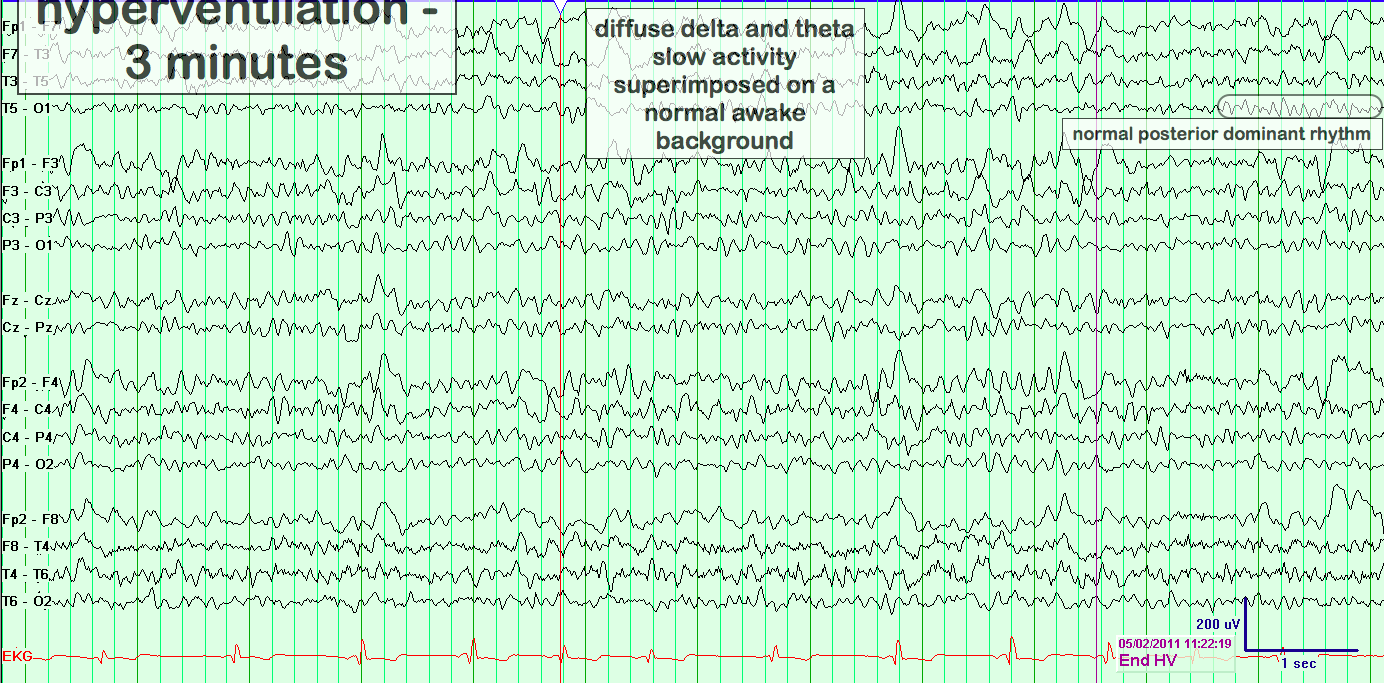

hyperventilation

Annotations: